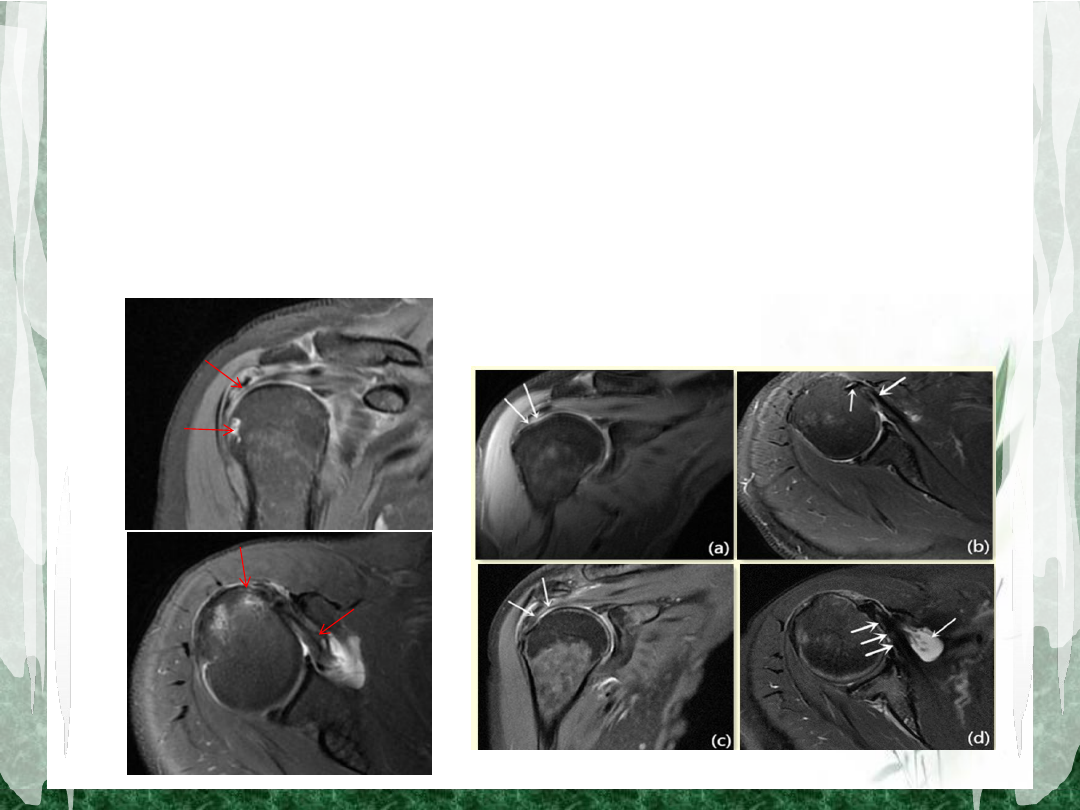

部分性肩袖损伤

全层肩袖损伤

滑囊侧损伤

关节侧损伤

影像学表现

• MRI

在斜冠状位和斜矢状位

T2

抑脂像显示肩袖信

号不同程度增高、边缘毛糙;肌腱局部连续性中

断、断端回缩、肩关节囊与肩峰下滑囊相通等;